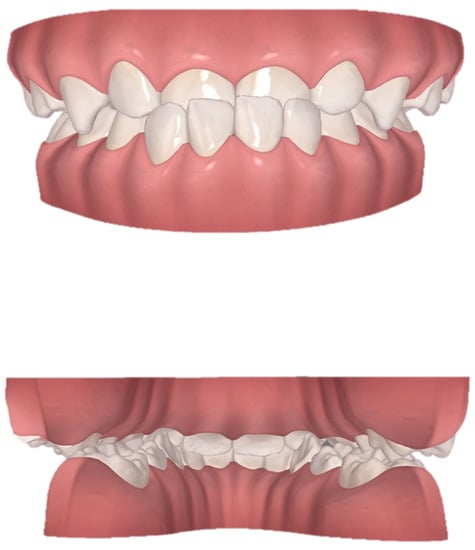

The clinical examination revealed a convex profile with protrusion of the upper and lower lips and hypertonia of the lip muscles (Figure 1). An intraoral examination identified a primary dentition phase. Centric occlusion examination indicated a Class III terminal molar relationship with a bilateral posterior scissor bite. The left posterior teeth presented a complete scissor bite with no contact on the occlusal surface, which was worse than their right counterparts (Figure 2 and Figure 3). An anterior crossbite was observed with a reverse overjet and overbite. Furthermore, the jaw could be retracted to display an edge-to-edge bite when guided backward. The mandibular incisors were upright, with the upper incisors slightly lingually inclined. The upper and lower dental midlines were aligned with the facial midline. No functional mandibular shift was observed when the mouth was open, and no clicking or pain was detected in the TMJ area. Moreover, habitual mandibular protraction at rest and during speech was observed.

We instructed the patient to wear each aligner continuously for 22 h daily and scheduled a monthly checkup. A total of 28 aligners were designed, and a program that required changes every seven days was implemented. Neither cases of detachment nor complaints of pain, discomfort, or impairment of function were reported. When the patient wore the 8th aligner, the anterior crossbite was corrected with convex profile improvement (Figure 10). With the 20th aligner, the posterior scissor bite was also corrected by maxillary narrowing and mandibular widening (Figure 11). Until the 25th aligner, nearly all of the chief complaints were settled, except for the insufficient tightness of occlusion on the right posterior teeth.

Figure 3. View of scissor bite details of the initial digital models.